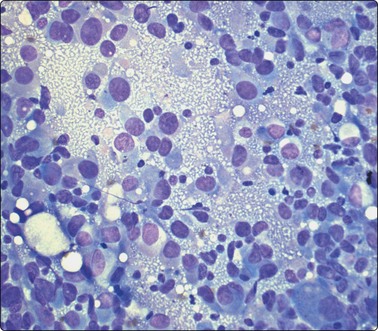

image image

Fig. 5.6 Reactive lymphadenopathy

(A) Smear derived from germinal center; loose tissue fragment of dendritic reticulum cells with ovoid nuclei and granular chromatin, centroblasts, centrocytes and some lymphocytes; syncytial background of pale cytoplasm; (B) Mixed population of lymphoid cells; two nuclei of dendritic reticulum cells with granular chromatin and small distinct nucleoli lower mid (MGG; HP).

The reactive pattern is variable depending on the degree of stimulation, the number and size of germinal centers and on whether the sample derives mainly from a germinal center or from interfollicular or paracortical tissue. Germinal center material is represented by poorly defined tissue fragments composed of centroblasts, centrocytes, ‘tingible body’ macrophages (Figs 5.4, 5.5), and a number of lymphocytes which adhere to the syncytial cytoplasm (pale gray/violet in MGG) of dendritic reticulum cells (Fig. 5.6A). Dendritic reticulum cells have oval or round nuclei with a smooth nuclear membrane, a coarsely granular, uniformly distributed chromatin and small distinct nucleoli (Fig. 5.6B). The cytoplasm is dispersed in the background. A smear, which derives mainly from interfollicular tissue, consists predominantly of lymphocytes with a variable but much smaller number of scattered immunoblasts, plasma cells, non-specific histiocytes and endothelial cells (Fig. 5.7). Multiple biopsies diminish the bias caused by selective sampling.